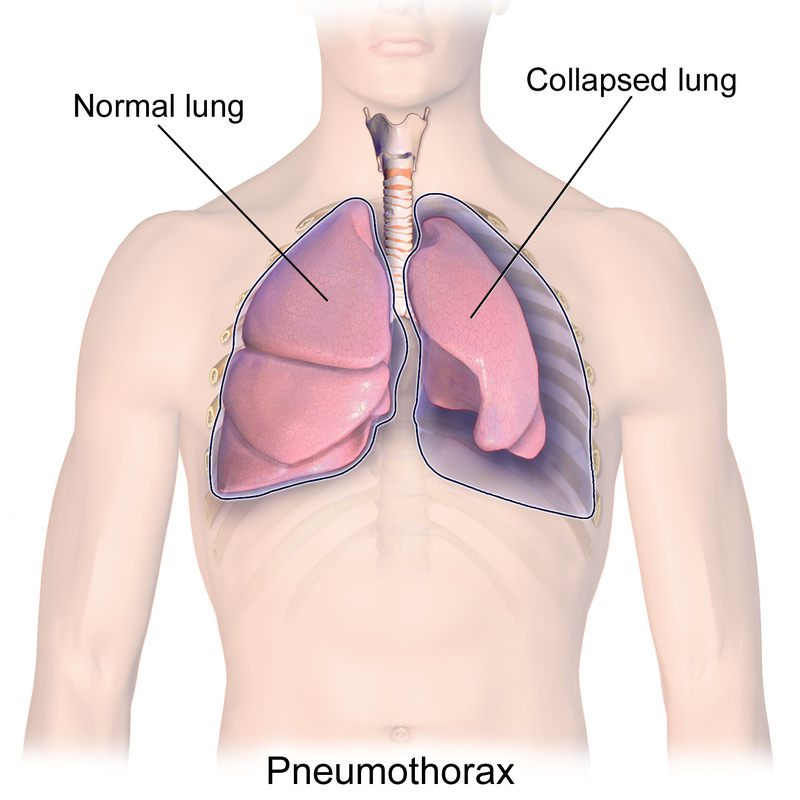

Computer-aided diagnosis for medical imaging is a well-studied field that aims to provide real-time decision support systems for physicians. These systems attempt to detect and diagnose a plethora of medical conditions across a variety of image diagnostic technologies including ultrasound, x-ray, MRI, and CT. When designing AI models for these systems, we are often limited by little training data, and for rare medical conditions, positive examples are difficult to obtain. These issues often cause models to perform poorly, so we needed a way to design an AI model in light of these limitations. Thus, our approach was to incorporate expert domain knowledge into the design of an AI model. We conducted two qualitative think-aloud studies with doctors trained in the interpretation of lung ultrasound diagnosis to extract relevant domain knowledge for the condition Pneumothorax. We extracted knowledge of key features and procedures used to make a diagnosis. With this knowledge, we employed knowledge engineering concepts to make recommendations for an AI model design to automatically diagnose Pneumothorax.

翻译:医学成像的计算机辅助诊断是一个研究周全的领域,目的是为医生提供实时决策支持系统。这些系统试图检测和诊断各种图像诊断技术,包括超声波、X光、MRI和CT等多种医疗条件。在为这些系统设计AI模型时,我们往往受到很少的培训数据的限制,对于罕见的医疗条件,很难获得积极的例子。这些问题往往导致模型运行不良,因此我们需要一种方法,根据这些局限性设计AI模型。因此,我们的方法是将专家领域知识纳入AI模型的设计中。我们与受过肺超声波诊断解释培训的医生进行了两次定性智囊研究,以获取有关肺部细胞病症的相关领域知识。我们利用这些知识获取了用于诊断的关键特征和程序的知识。我们利用这些知识,运用了知识工程概念,为用于自动诊断肺部细胞的AI模型设计提出建议。